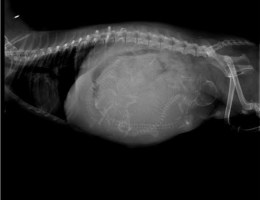

In prossimità del 57° giorno dal primo accoppiamento, sarà necessario eseguire una RADIOGRAFIA che ci permetterà di stabilire con certezza il numero dei cuccioli presenti nell’utero e la posizione, così da avere la conferma della direzione in uscita dei cuccioli al momento del parto (testa o podice).